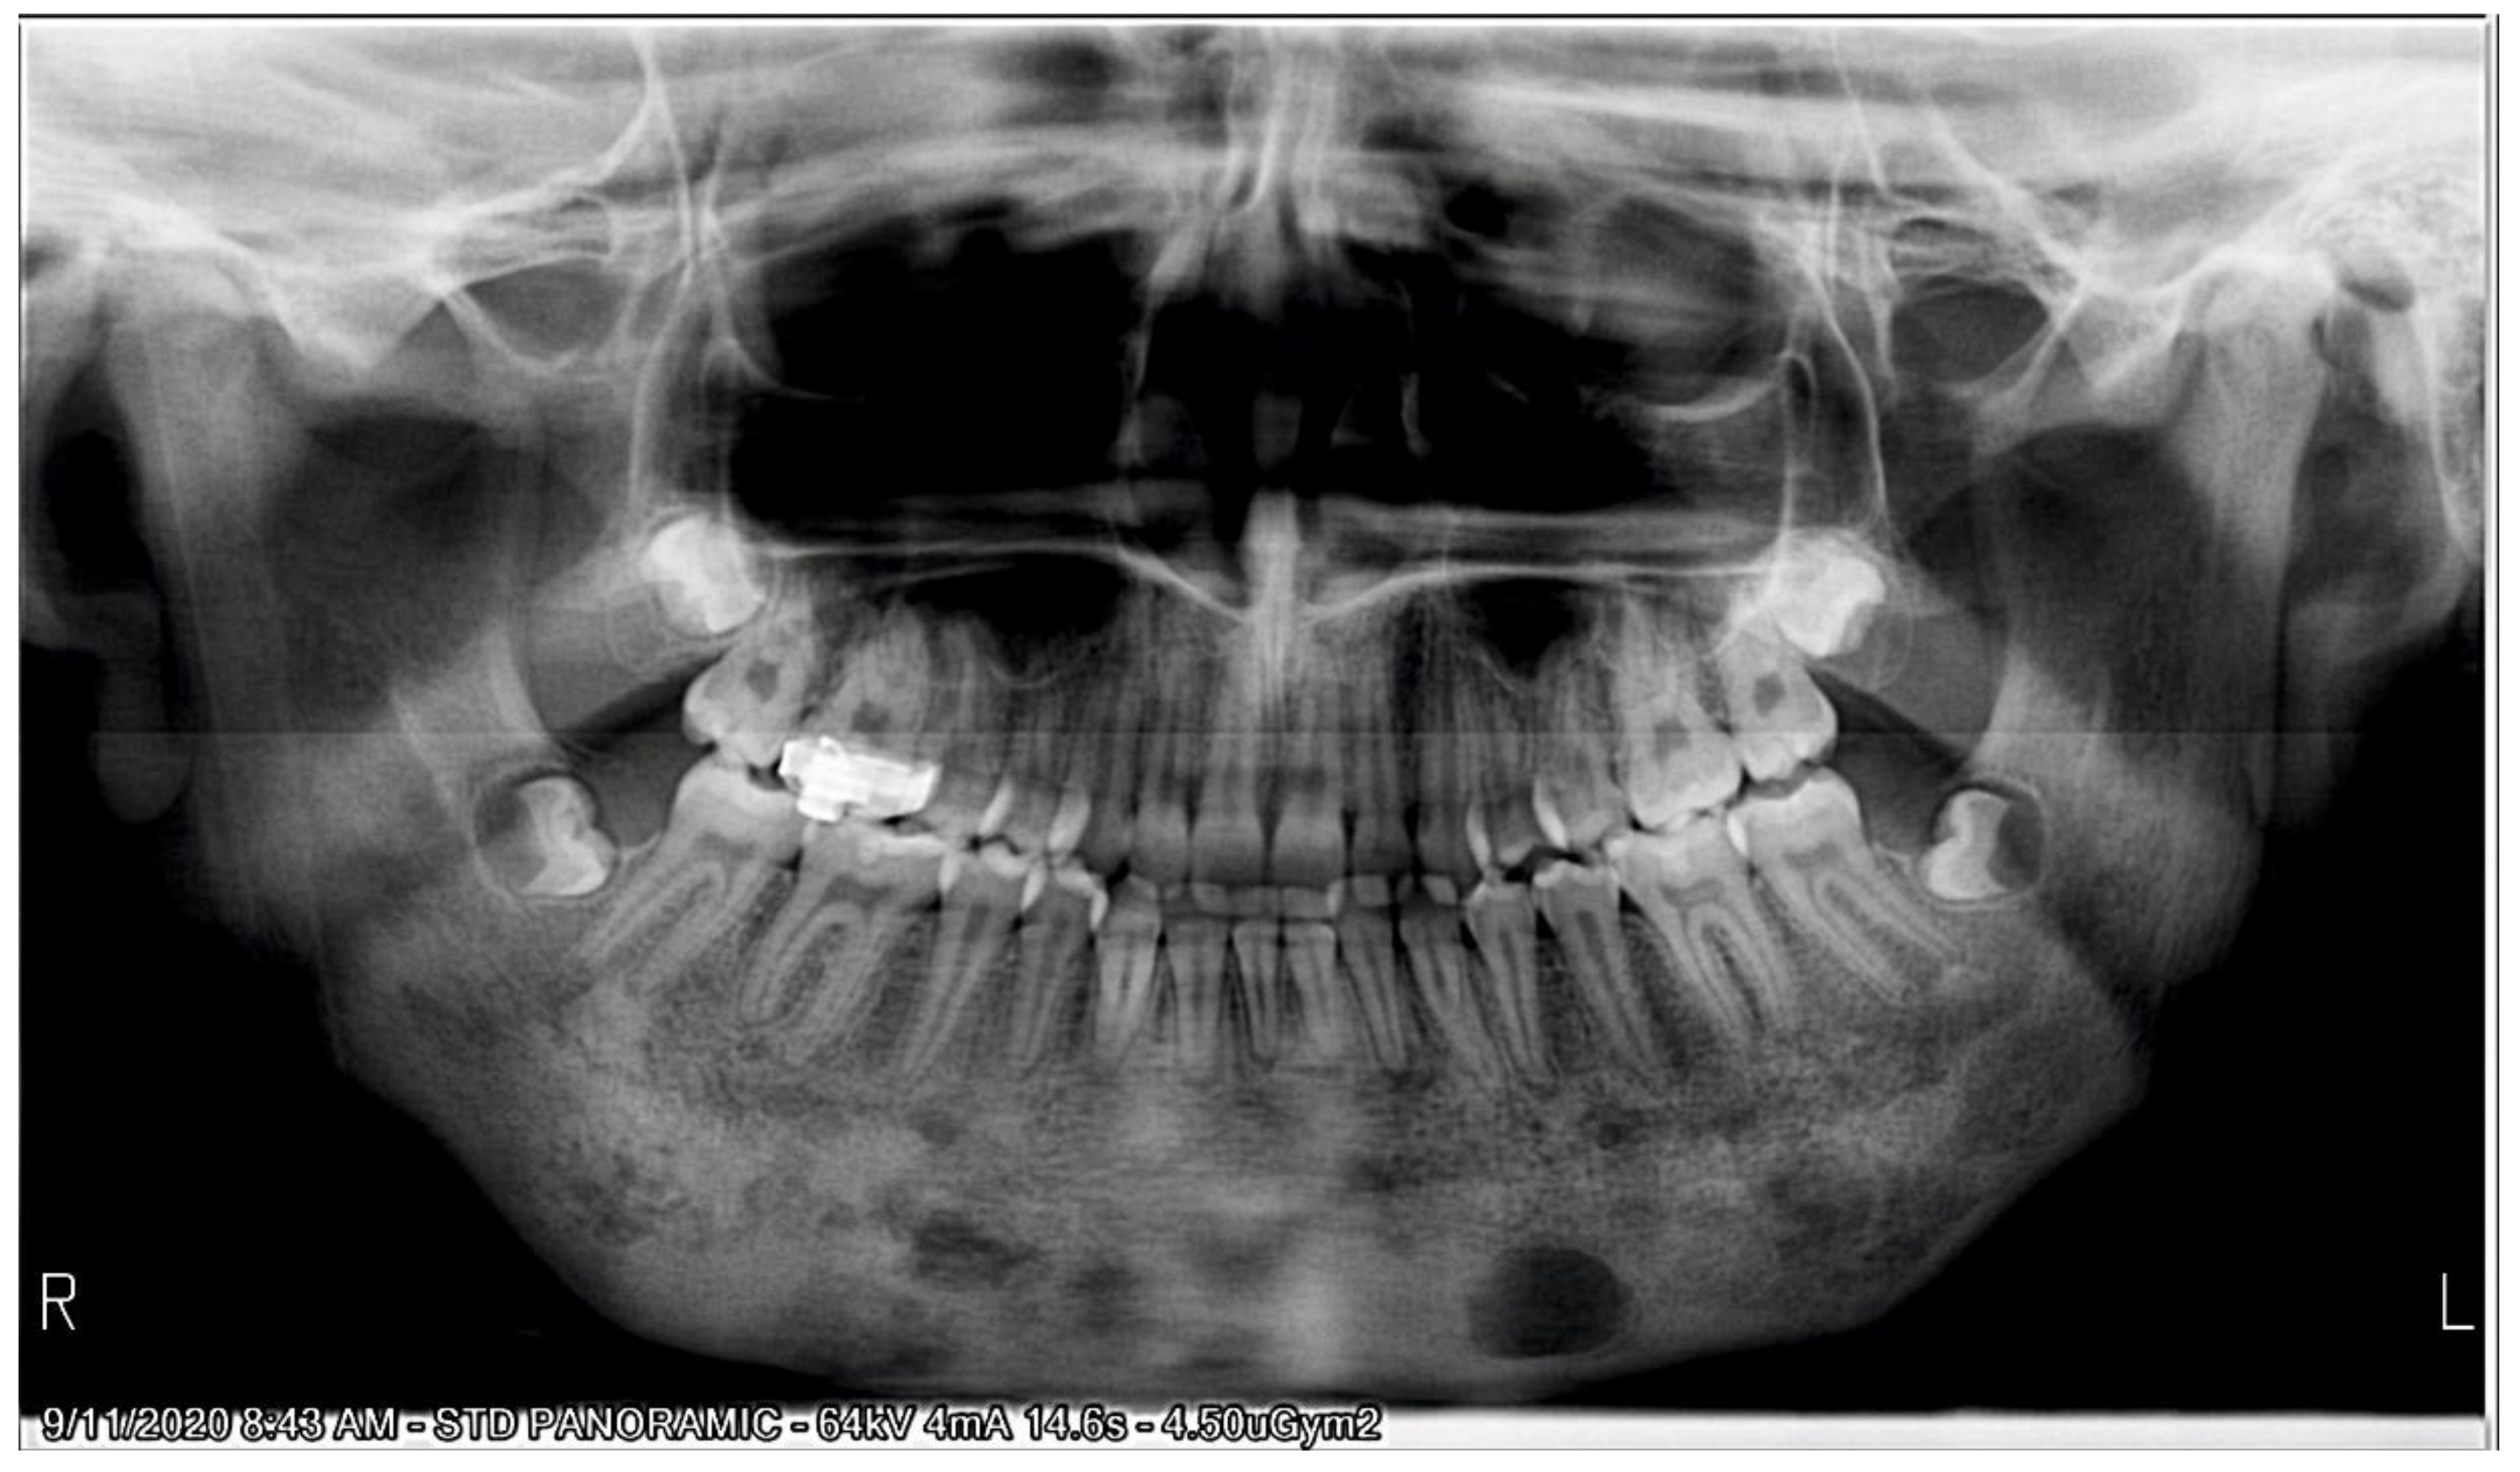

2.1. Initial Diagnosis and Initial Surgical Management

2.2.1. Initial Examination